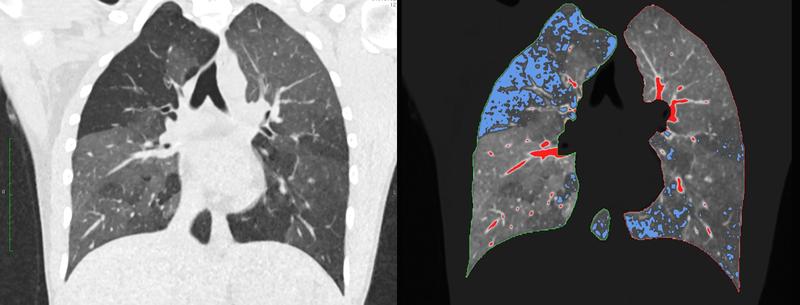

Röntgenkongress: Neuronales Netz blickt tief in die Lunge

„Wenn wir uns als Radiologen CT-Bilder ansehen, dann sehen wir helle und dunklere Areale und beurteilen das Organ anhand dieser Helligkeitsunterschiede“, sagt…